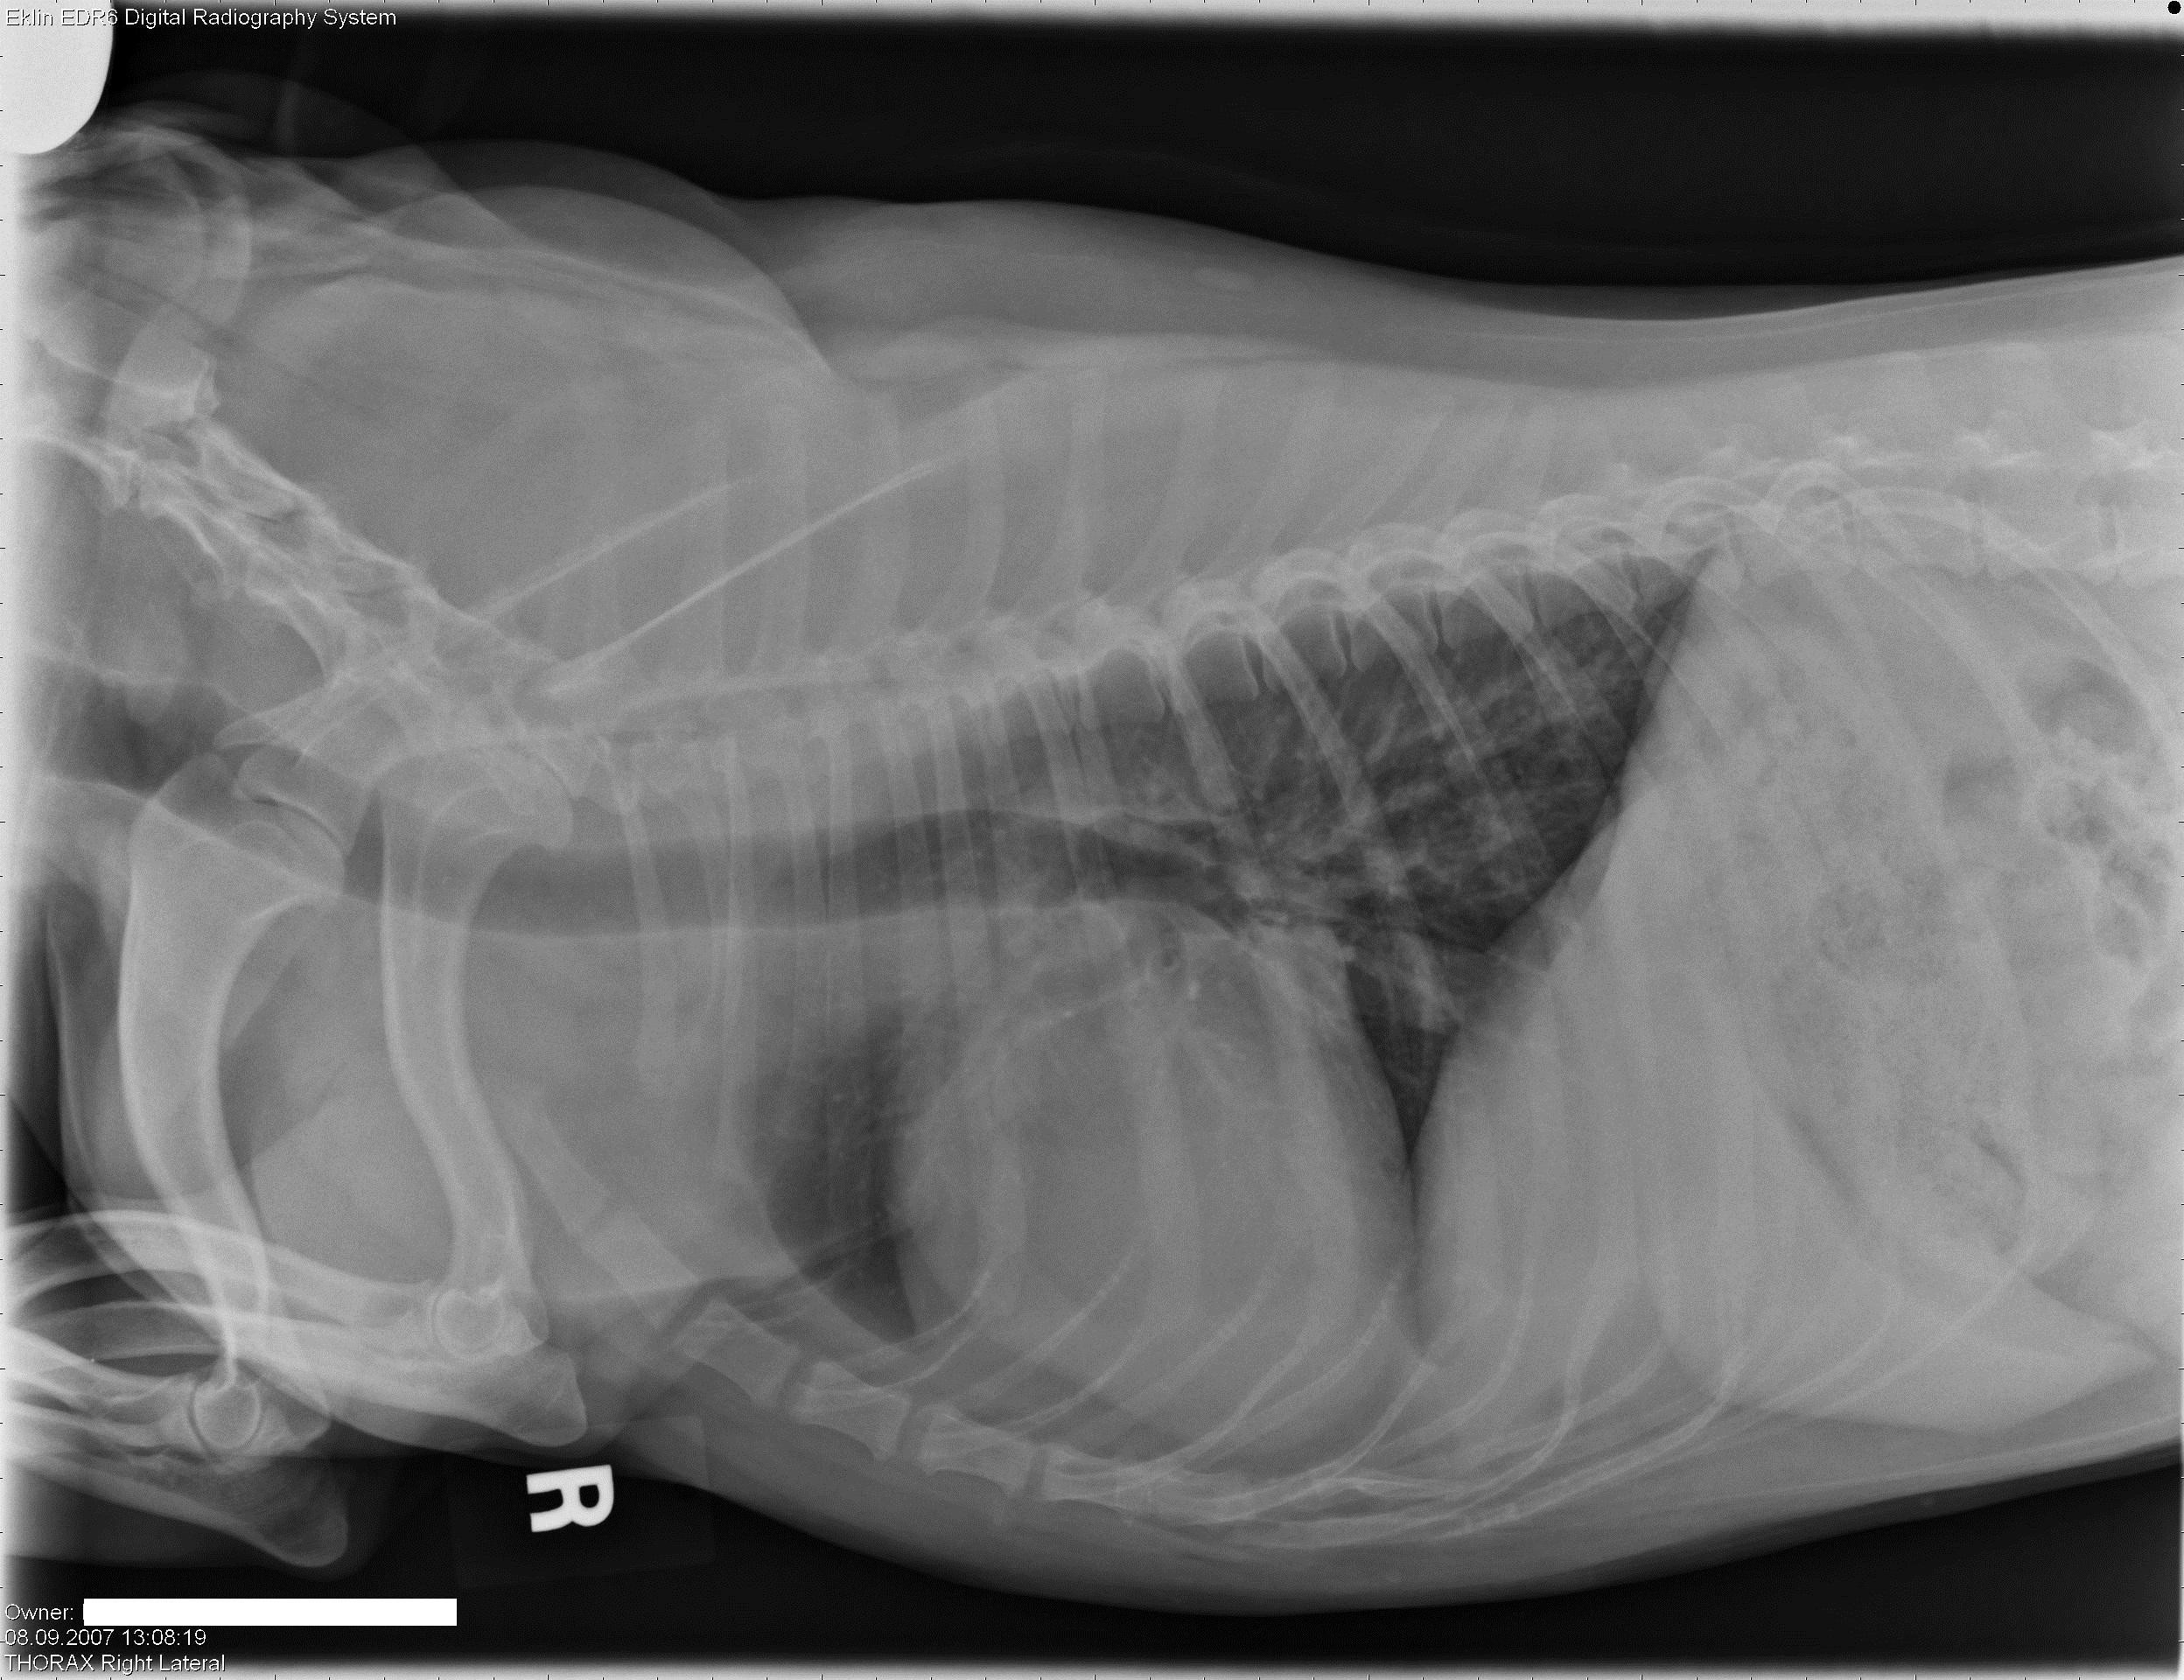

Een 10 jaar oude, mannelijk, gecastreerde hond wordt bij je aangeboden met erge tenesmus.Â

Hieronder vind je 5 Röntgen foto’s thorax en abdomen. Gebruik de pijltjes om erdoor te schuiven, of klik op de foto om te vergroten.